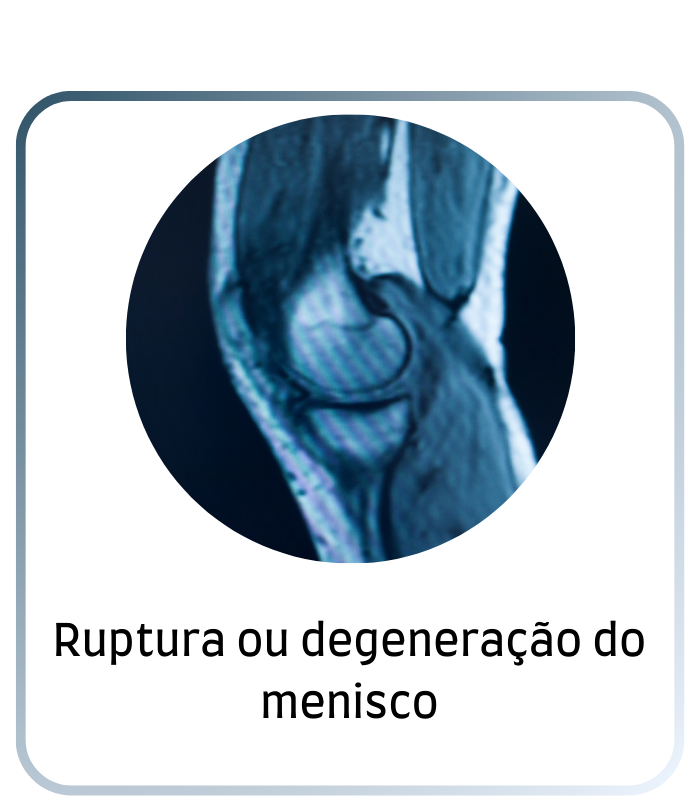

Corrigem rupturas que causam dor, travamento e perda funcional.